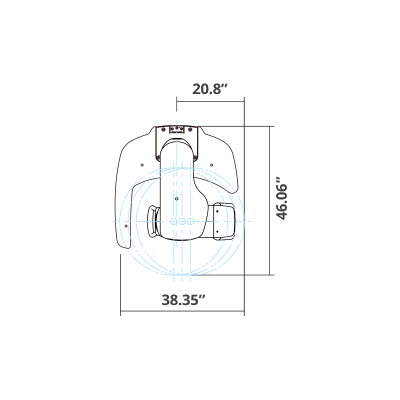

| TYPE | TOP VIEW | FRONT VIEW |

|---|---|---|

|

PaX-i (Pano) |

|

|